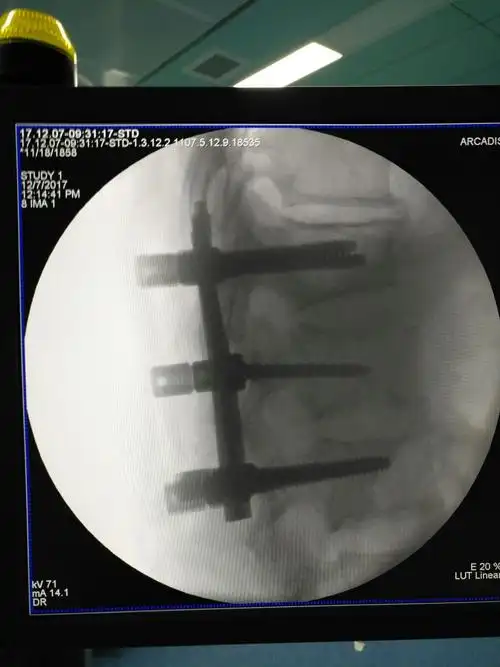

胸腰椎骨折经皮椎弓根螺钉内固定术

急性腰椎骨折经皮复位钉棒内固定术

腰4腰5椎弓根螺钉顺利置入

市一院骨六科完成经皮椎弓根钉棒内固定术治疗腰椎压缩性骨折一例